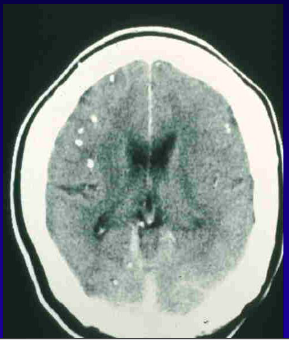

What is the orgnaism and diagnosis?

Neurocysticercosis T.Solium

What is this and what does it cause?

A

Calcified lesions of NCC. Taenia Solium. Can still cause seizures.

How well did you know this?

Calcified lesions of neurocysticercosis Chronic epilepsy